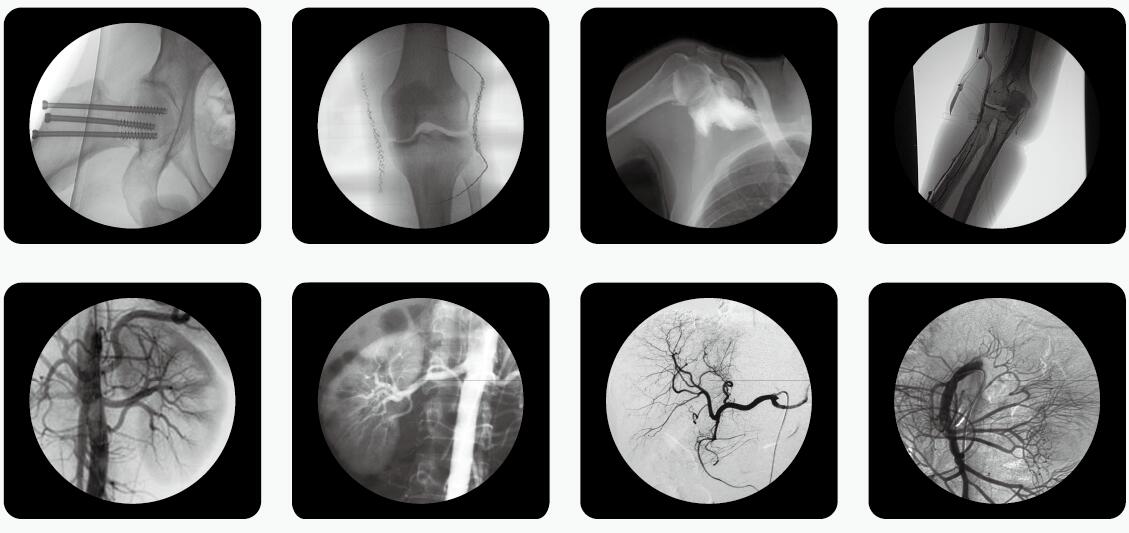

如何在滿足影像診療質量的同時,有效地控制輻射危害,已成為放射學發展中的一個亟待解決的重要問題。C臂透視機是骨科手術中使用較多的一款放射性醫療設備。

C臂透視機

骨科醫生用C臂機透視比較多,如何在手術過程中實施安全防護措施,極大限度地減少電離輻射對人體的危害,顯得尤為重要,以下是小編為大家整理了C臂透視機防護三大原則,來和大家一起分享。